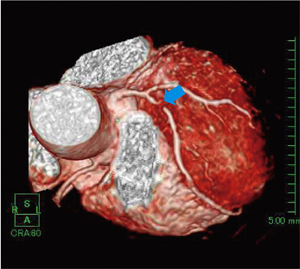

図1〜3は,MRIで撮像された冠動脈の解析結果画像である。図1はVR表示で,LAD#6に狭窄を見ることができる。図2の読影画面では,任意の部分にカーソルを合わせて,連動する複数のMPRによりその部分の詳細を確認する。図3のPWMIP表示では,末梢の血管を表示できるため,全体像の詳細な把握に有用である。また,血管外径を計測し,面積による狭窄率の計算も行うことができる。さまざまな表示方法を組み合わせ連動させることで,短時間で詳細な解析や読影を行うことができるものと考える。

図1 VR表示

LAD#6に狭窄(↓)を認める。